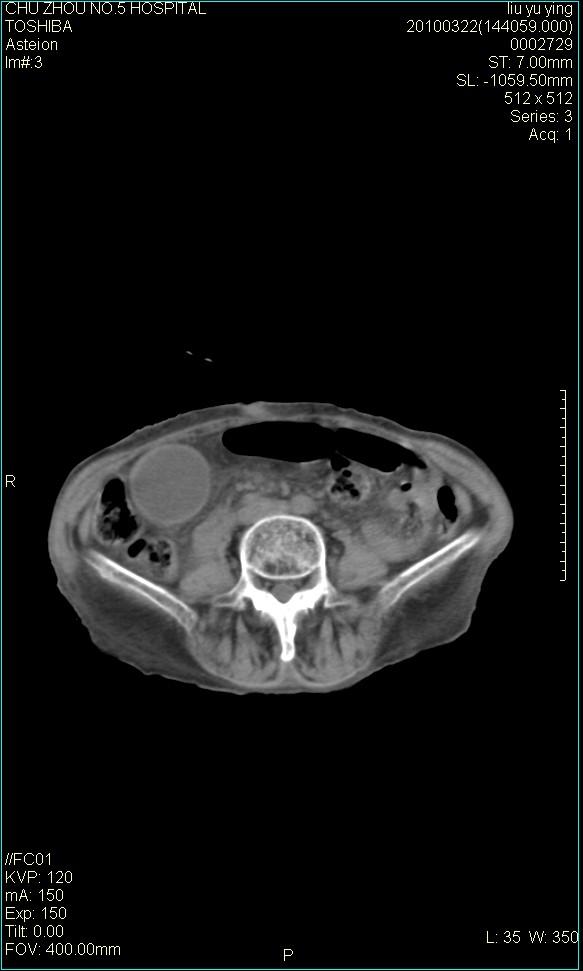

以下是引用科室第一人在2010-3-23 6:50:00的发言:[br]胆总管下段梗阻,多为肿瘤性病变,巨形胆囊,胆囊炎胆囊窝积液。[br]双侧胸腔积液,右降

以下是引用随光逐影在2010-3-23 8:12:00的发言:[br]1)胆系低位梗阻(肝内外胆管扩张,胆囊增大),原因待查。2)胆囊炎。3)双侧少量胸腔积液。4)降主动脉迂曲。